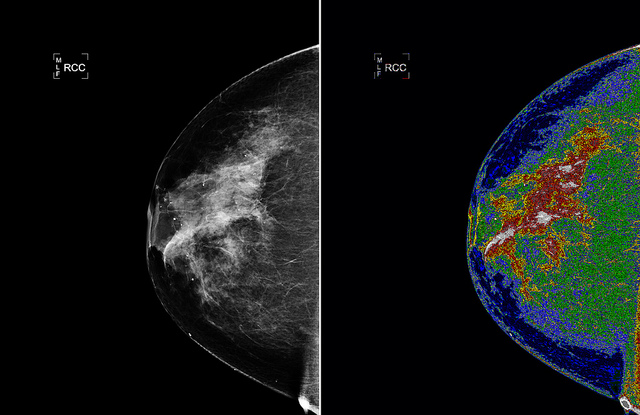

Researchers Libertario Demi, Ruud van Sloun and Massimo Mischi have now developed a variant of the echography method that is suitable for breast investigation. The method is known as Dynamic Contrast Specific Ultrasound Tomography. Echography with microbubbles uses the fact that the bubbles will vibrate in the blood at the same frequency as the sound produced by the echoscanner, as well as at twice that frequency; the so-called second harmonic. By capturing the vibration, you know where the bubbles are located. But body tissue also generates harmonics, and that disturbs the observation.

For the new method the researchers are using a phenomenon that Mischi happened upon by chance and later investigated its properties together with Demi. They saw that the second harmonic was a little delayed by the gas bubbles. The researchers have now developed a new visualization method. The more bubbles the sound-wave encounters on its route, the bigger the delay. By measuring the delay, the researchers can thus localize the gas bubbles and do so without any disturbance because the harmonic generated by the body tissue is not delayed, and is therefore discernible. This difference, however, can only be seen if the sound is captured on the other side. So this method is perfectly suited to organs that can be approached from two sides, like the breast.